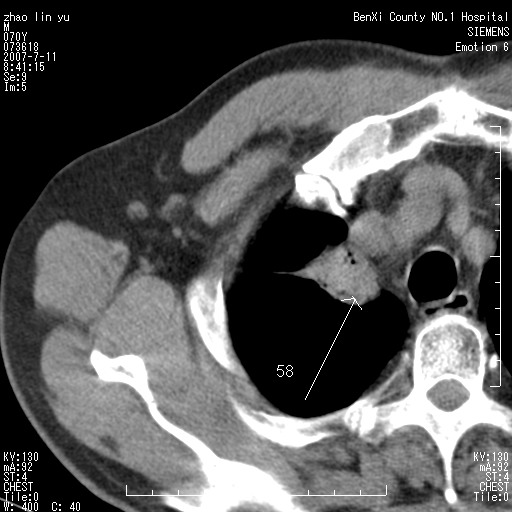

以下是引用王靖旗在2007-7-10 17:12:00的发言:[br] 男、70、咳嗽两个月,半年前换瓣手术,胸片未见异常,于昨天行x片发现右肺上野大片影,行ct扫描,这里是减薄图像,余肺正常。明天晚上会有增强扫描片,到时我会上传。[br][br] 冠状位请大家细看,应该是有意义的,[br][br] 请大家先看平扫发表意见。[br][br]

以下是引用zhangzhongshou在2007-7-10 21:43:00的发言:[br]右肺上叶周围型肺癌,以孤立型细支气管肺泡癌可能性大。